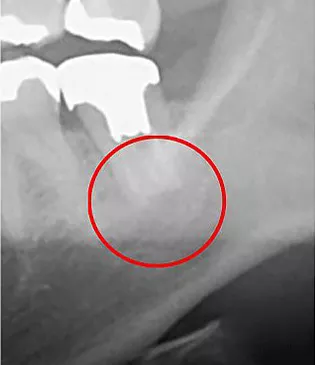

CTはマイクロスコープ(歯科用顕微鏡)同様、治療部位を「見える化」させる機器です。通常のレントゲン(デンタルエックス線写真)でも大まかには判断可能ですが、CTを用いる事で、デンタルエックス線写真では発見できないような微細な病変も発見することが出来ます。

赤丸部分が問題の個所になりますが、一般的なレントゲンではしっかりと確認することは出来ませんが、

治療をする上で、最初の診査診断が非常に重要となります。

なぜなら、最初の段階で正確な診断を下さなければ、誤った治療法を選択し、最終的には残せる歯も残せなくなる恐れがあるためです。

当院では「見える化」できるCTを活用し、誤った診査診断を回避するための細心の注意を払っております。

CT画像

レントゲン画像